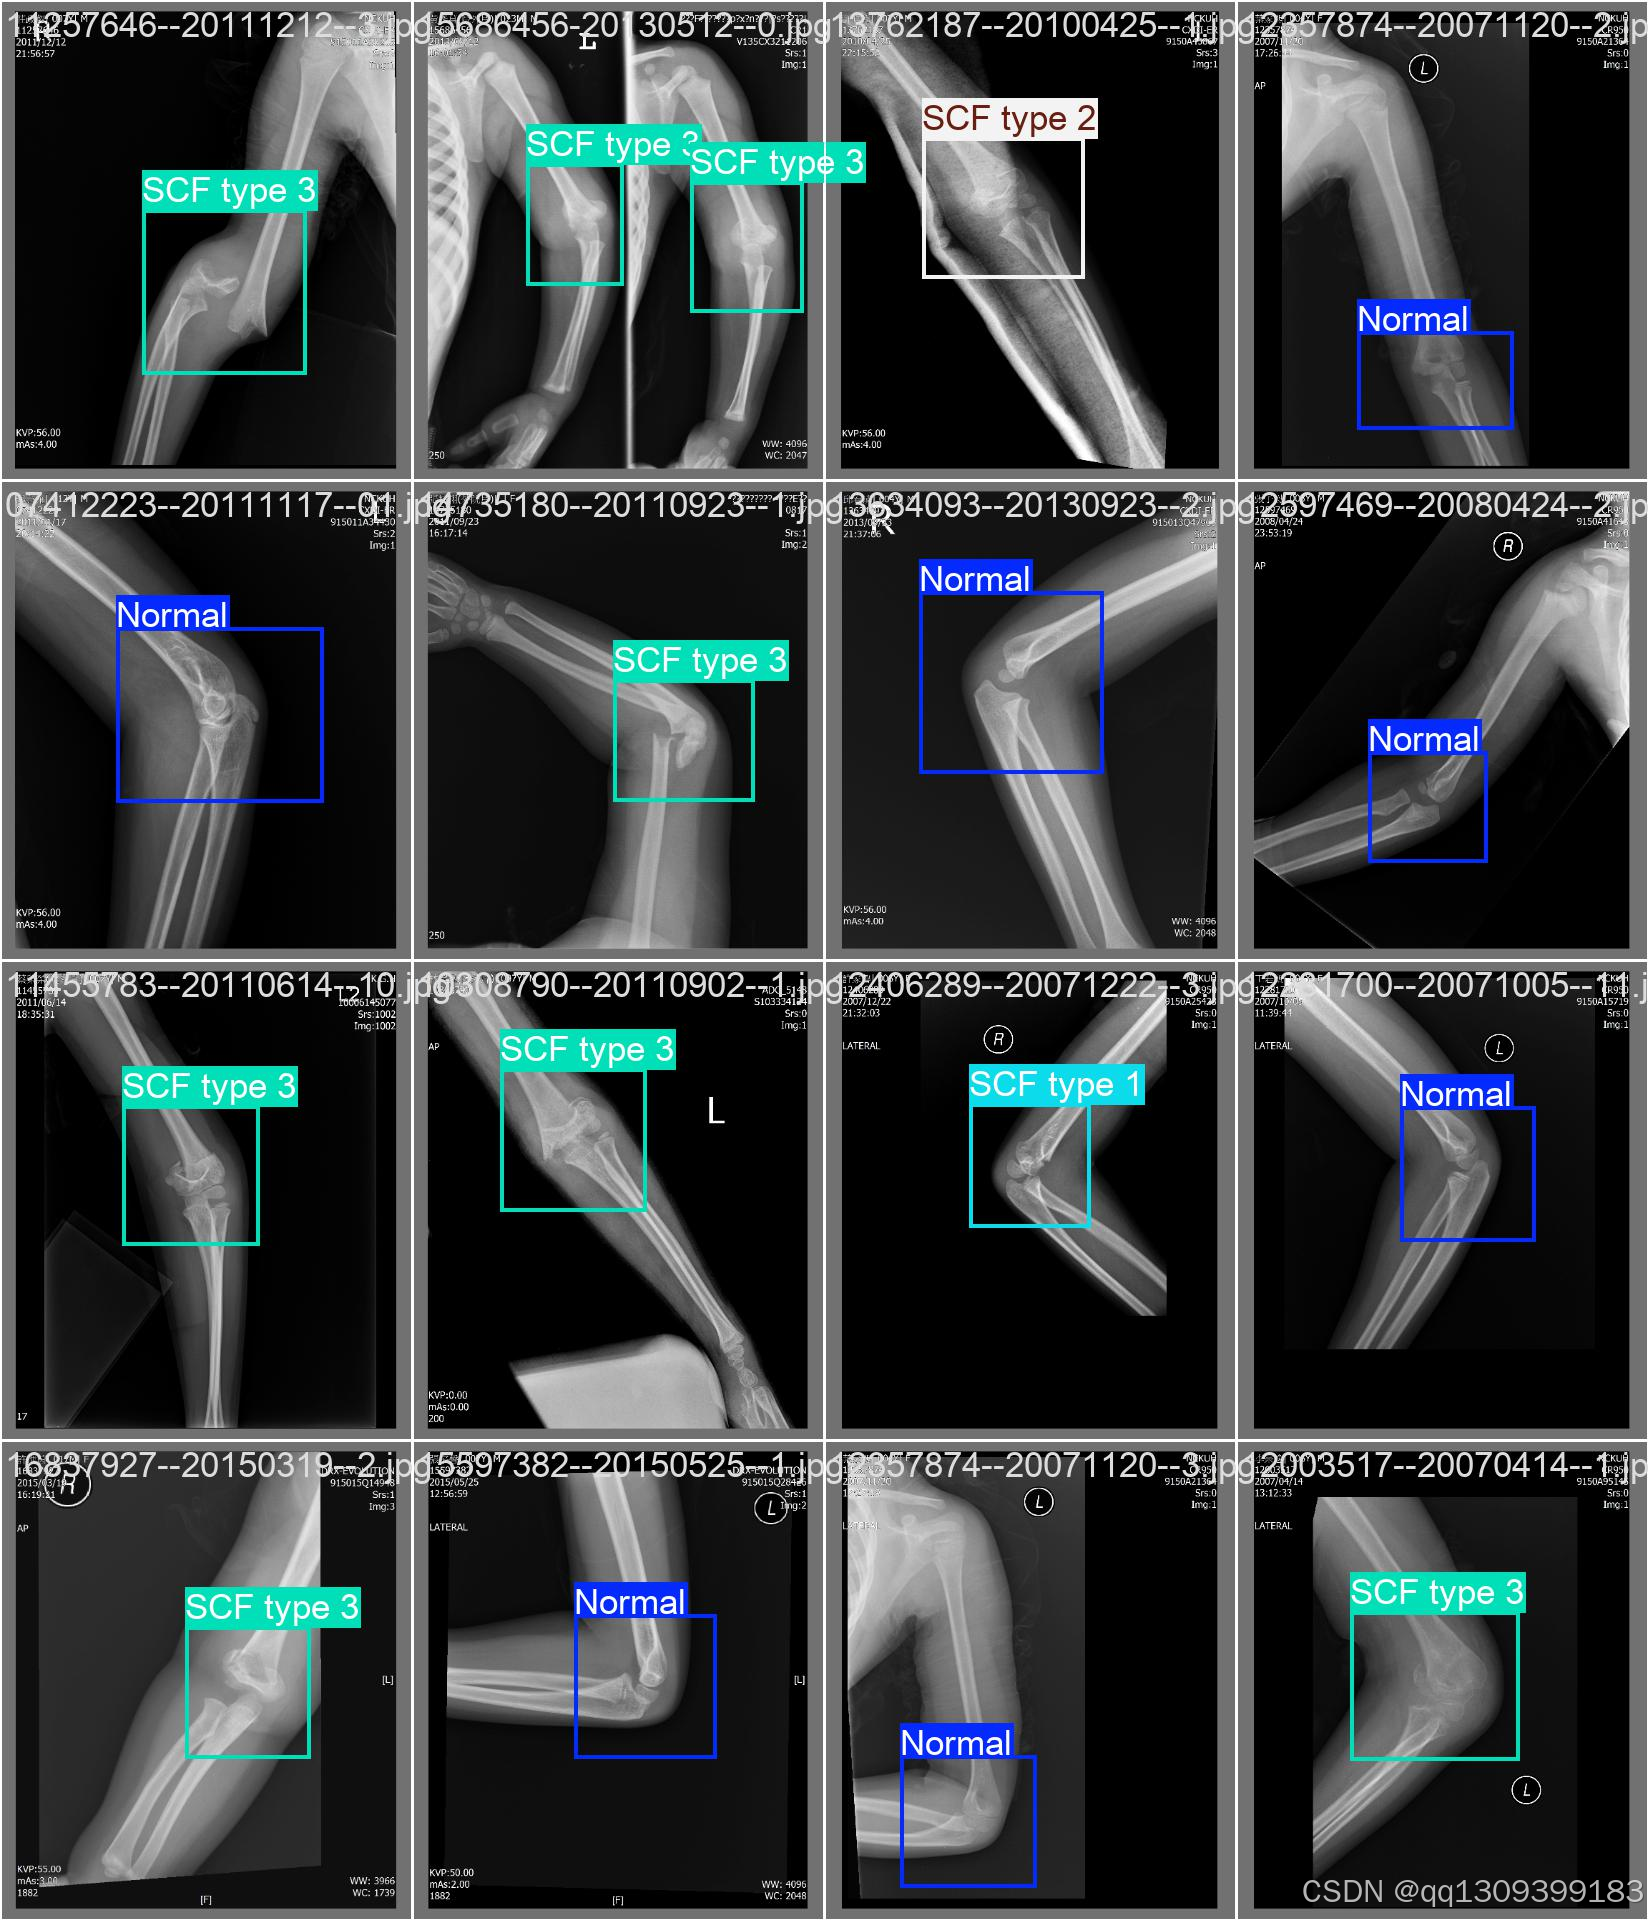

结果展示